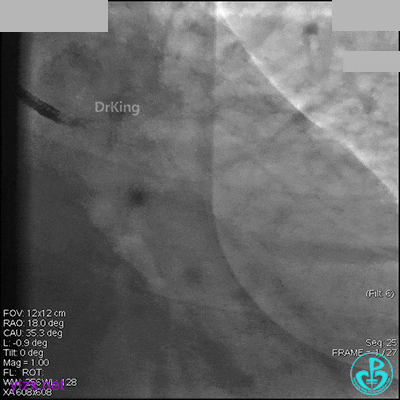

先处理前降支开口严重狭窄并顺利植入前降支到左主干支架。

没有说明是否进行了右冠脉介入治疗。